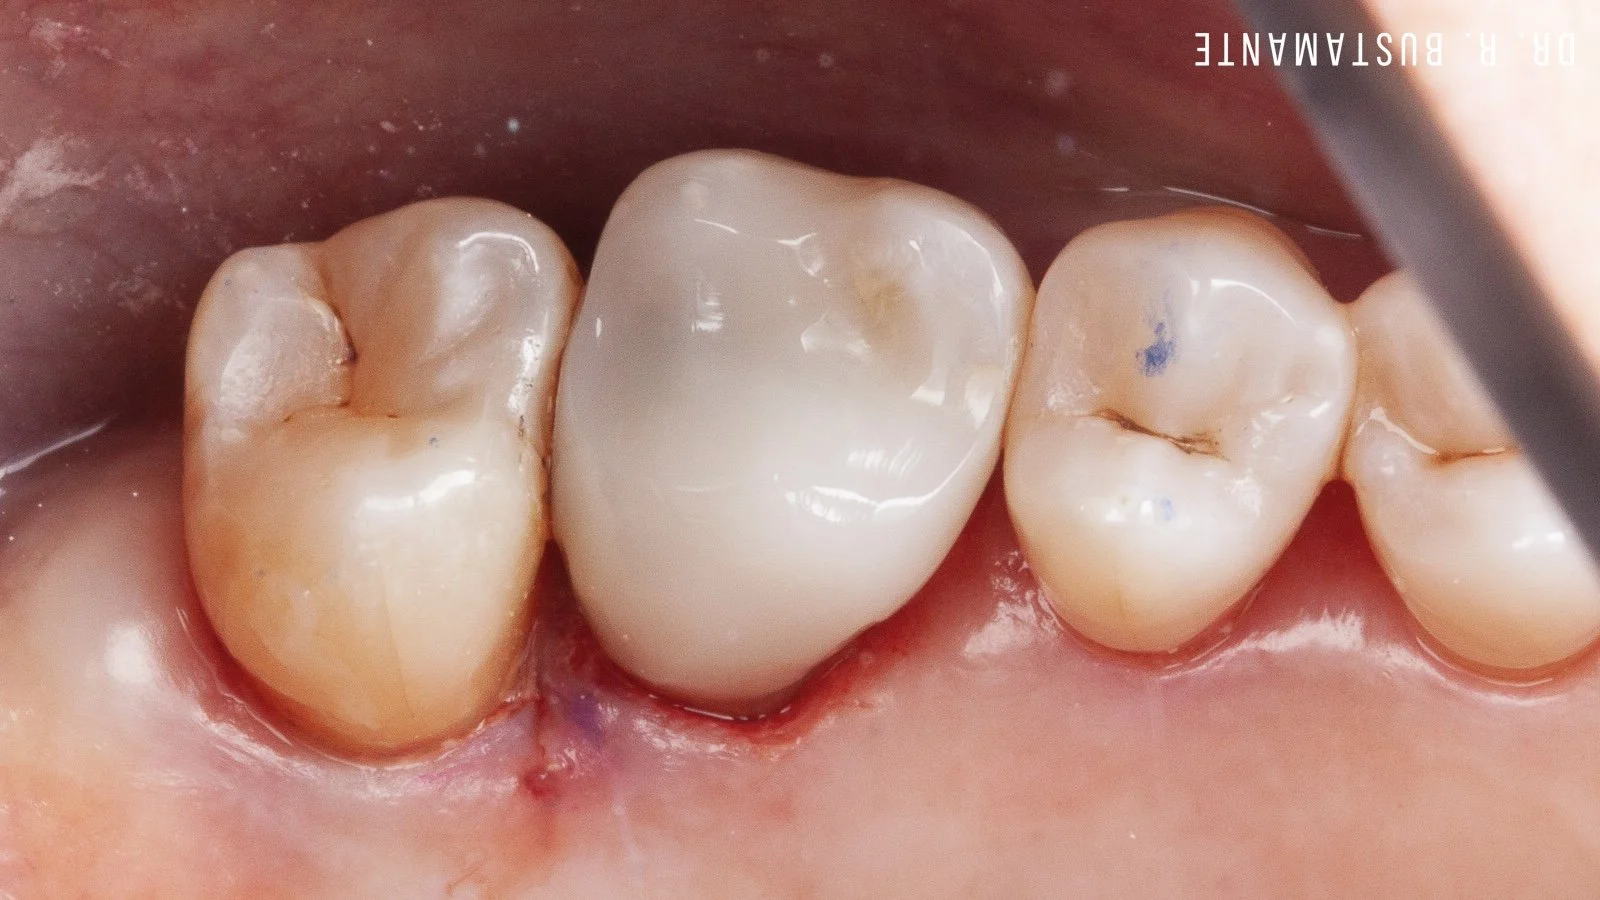

The images displayed here showcase actual cases completed by Dr. Bustamante, reflecting the artistry and precision of this technique. Please note that while Bioclear is ideal for many, a personalized consultation will determine the best treatment to achieve your perfect smile. Experience the confidence of a beautifully restored smile with Bioclear.

The Bioclear Method can rejuvenate the shape, size, and fit of your teeth. Bioclear is a minimally invasive, conservative alternative to rejuvenating worn out, broken, discoloured, and chipped teeth.

Replacing failing white and silver fillings.